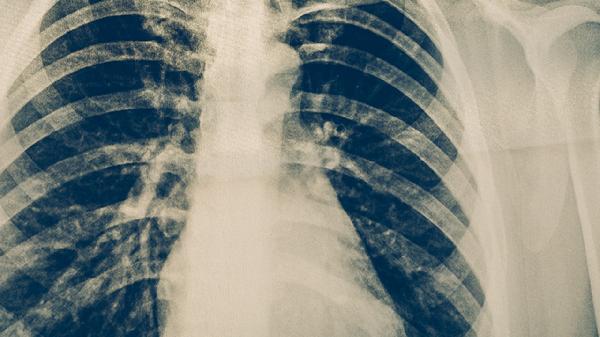

防治肺結(jié)核可以適量吃富含優(yōu)質(zhì)蛋白的食物如雞蛋、牛奶,以及富含維生素A的西藍(lán)花、富含維生素C的柑橘類水果、富含鋅的牡蠣等,同時(shí)需遵醫(yī)囑使用異煙肼片、利福平膠囊、吡嗪酰胺片、乙胺丁醇片、鏈霉素注射液等抗結(jié)核藥物。肺結(jié)核患者應(yīng)保證營養(yǎng)均衡,避免辛辣刺激食物,并嚴(yán)格遵循規(guī)范化療方案。

肺結(jié)核患者應(yīng)保持每日熱量攝入不低于2000千卡,采用高蛋白、高維生素、適量礦物質(zhì)的飲食結(jié)構(gòu)。烹飪方式以蒸煮燉為主,避免油炸燒烤。保證每日飲水1500-2000毫升促進(jìn)藥物代謝。居住環(huán)境需通風(fēng)良好,每日紫外線消毒,餐具單獨(dú)使用并煮沸消毒。嚴(yán)格完成6-9個月規(guī)范治療,不可自行停藥,定期復(fù)查胸部影像學(xué)和痰菌檢測。密切接觸者應(yīng)進(jìn)行結(jié)核菌素試驗(yàn)篩查。